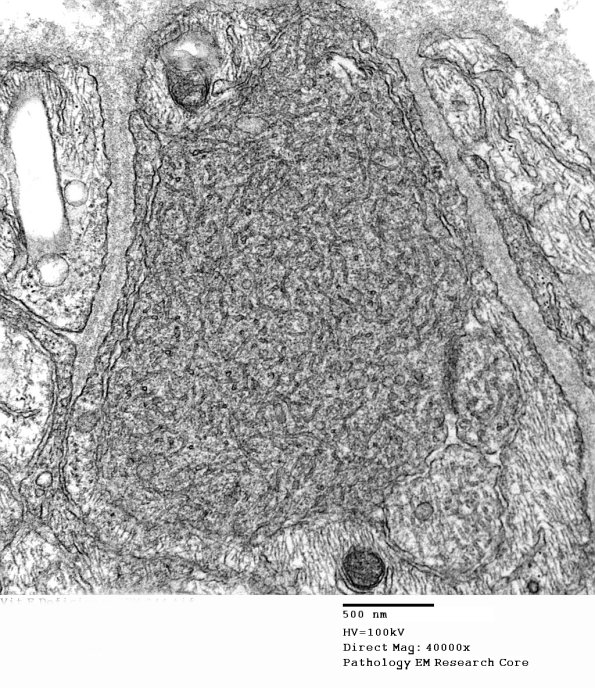

11Q2 Vit E Deficiency (EM_044 - Copy

Higher magnification of image #11Q1. (electron micrograph)